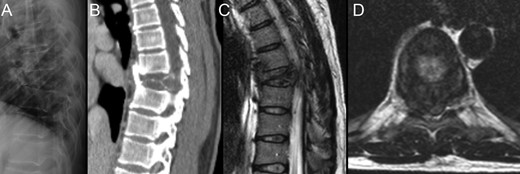

Due to the advanced stage of the lesion, with associated instability that could result in major neurologic deficits in a short time period, a total en bloc spondylectomy of T8 by a posterior-only approach was performed (Fig. 2). The operation followed the technique proposed by Tomita et al. and was complemented with anterior-column reconstruction with a titanium mesh filled with structural allograft, as well as pedicle screw instrumentation, from T6 to T10 (Fig. 3). During the procedure, the eighth dorsal nerve routes were sacrificed.